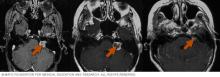

Brain scans showing Gamma Knife surgery results.

Gamma Knife surgery results

Gamma Knife surgery uses multiple tiny beams of radiation to shrink tumors. The left brain scan shows a pretreatment image of a noncancerous tumor — an image enhanced by the use of a special medium, called a contrast agent. At six months after treatment (middle image), the tumor appears slightly larger but doesn't take up as much of the contrast medium — it isn't as bright in the center. This indicates a positive treatment effect. At seven years (right scan), the tumor appears much smaller.